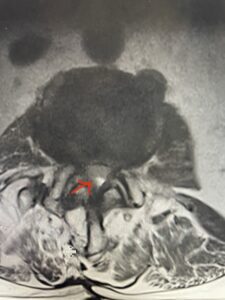

In patients who have lumbar spinal stenosis and significant cardio/pulmonary conditions, surgery is the last resort. However, some patients with these conditions may fail all means of conservative management where surgery becomes their only option for relief. In those patients, one should strive to do the least complex surgery that is necessary to get the job done for them. In this case study, we are confronted with a new problem in a 78 year-old male patient that was in poor medical condition who had had two prior lumbar laminectomies with resultant fusion and instrumentation from L4-S1. There was now retrolisthesis of L2-3 with severe stenosis (Fig.1)

Fig 1b: axial T2-weighted MRI demonstrating severe lumbar stenosis (red arrow)